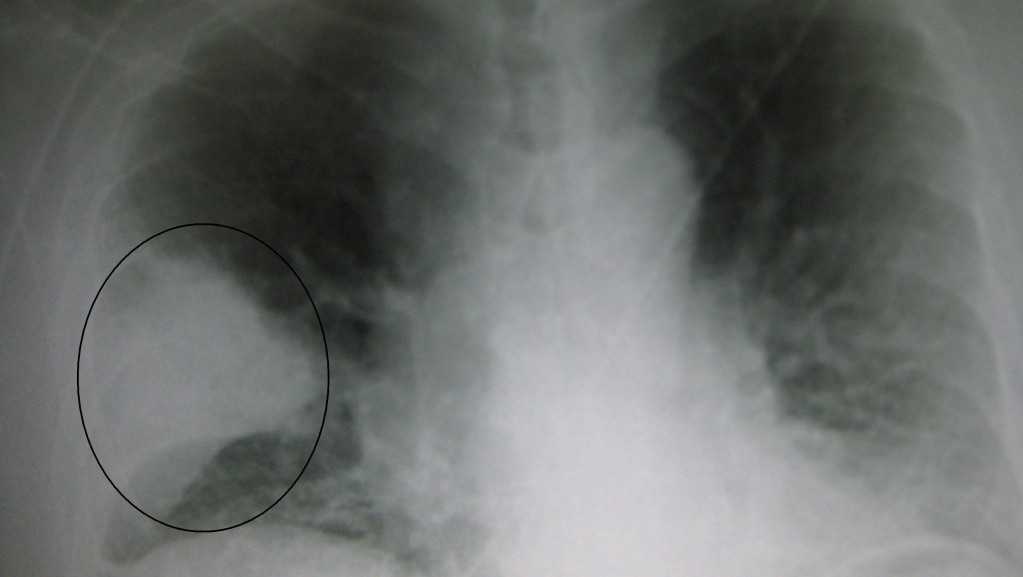

Inovativna terapija karcinom pluća pretvara u hroničnu bolest - Copyright profimedia